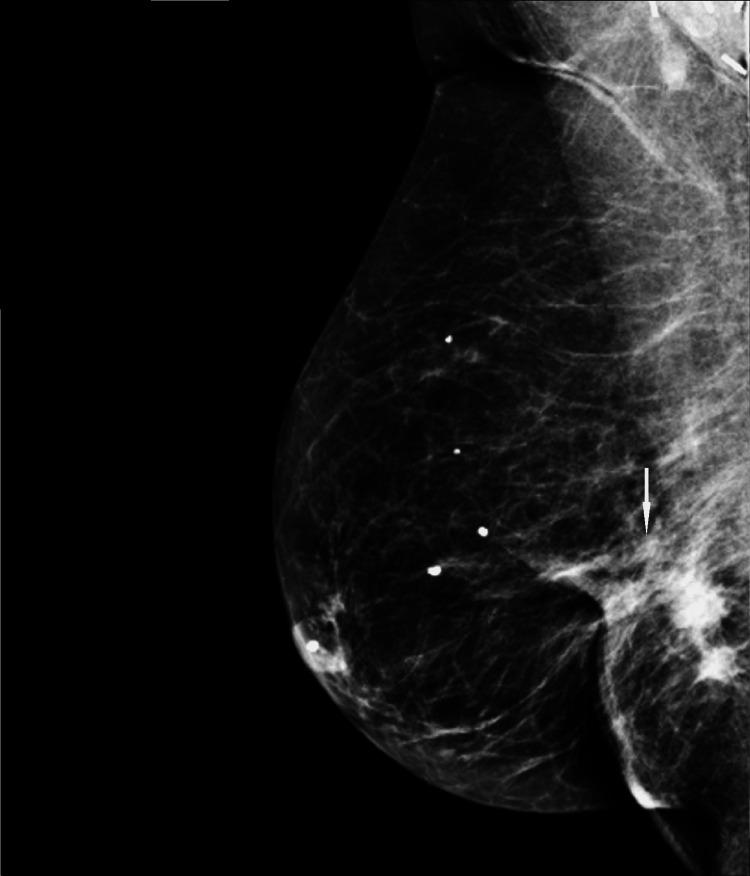

We describe a case of pathology-proven invasive lobular breast cancer (ILC) arising in a scar over 15 years after lumpectomy for previous invasive ductal carcinoma (IDC). The tumor was detected on screening mammography as a new focal asymmetry at the scar site and confirmed at diagnostic mammography. Ultrasound demonstrated an irregular, shadowing, hypoechoic mass at the scar site. Ultrasound-guided biopsy revealed poorly differentiated invasive lobular carcinoma. MRI and CT showed an irregular mass with pectoralis muscle invasion. Multimodality imaging findings are described. This is the first case to our knowledge reporting multimodality imaging findings of a breast cancer developing at the site of a surgical scar that is histologically different from the originally resected cancer.

我们描述了一例经病理证实的浸润性小叶乳腺癌(ILC)病例,该病例发生于先前因浸润性导管癌(IDC)行肿块切除术后15年以上的瘢痕处。肿瘤在筛查乳腺X线摄影中被检测为瘢痕部位新出现的局灶性不对称,并在诊断性乳腺X线摄影中得到证实。超声显示瘢痕部位有一个不规则、有阴影、低回声肿块。超声引导下活检显示为低分化浸润性小叶癌。MRI和CT显示有一个不规则肿块,侵犯胸大肌。描述了多模态成像结果。据我们所知,这是首例报告手术瘢痕部位发生的组织学上与最初切除的癌症不同的乳腺癌的多模态成像结果的病例。